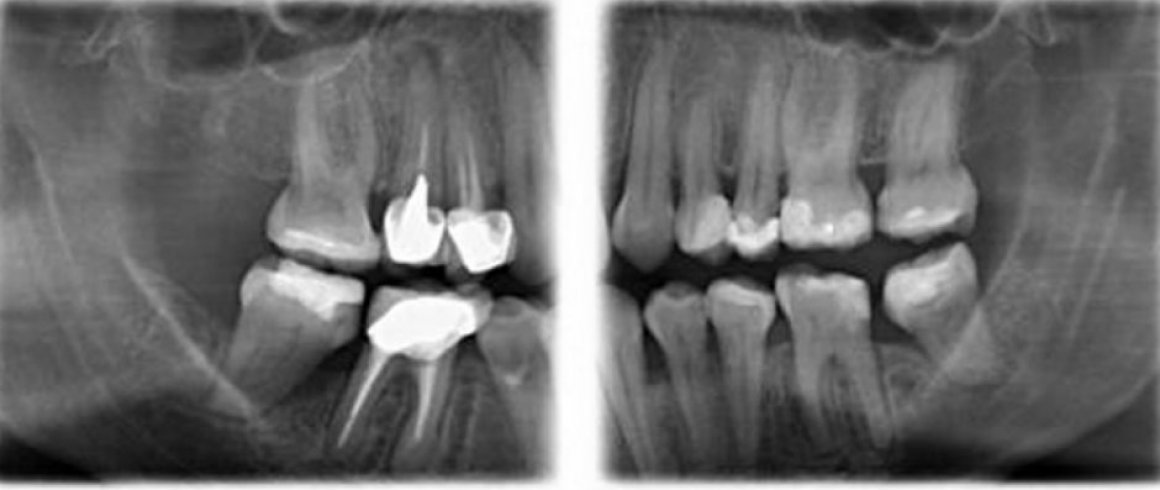

- Panorámica

- Tomografía

- Implantes

- A.T.M. (Boca abierta/Boca cerrada)

- Localización de Diente Impactado

- Área Patológica